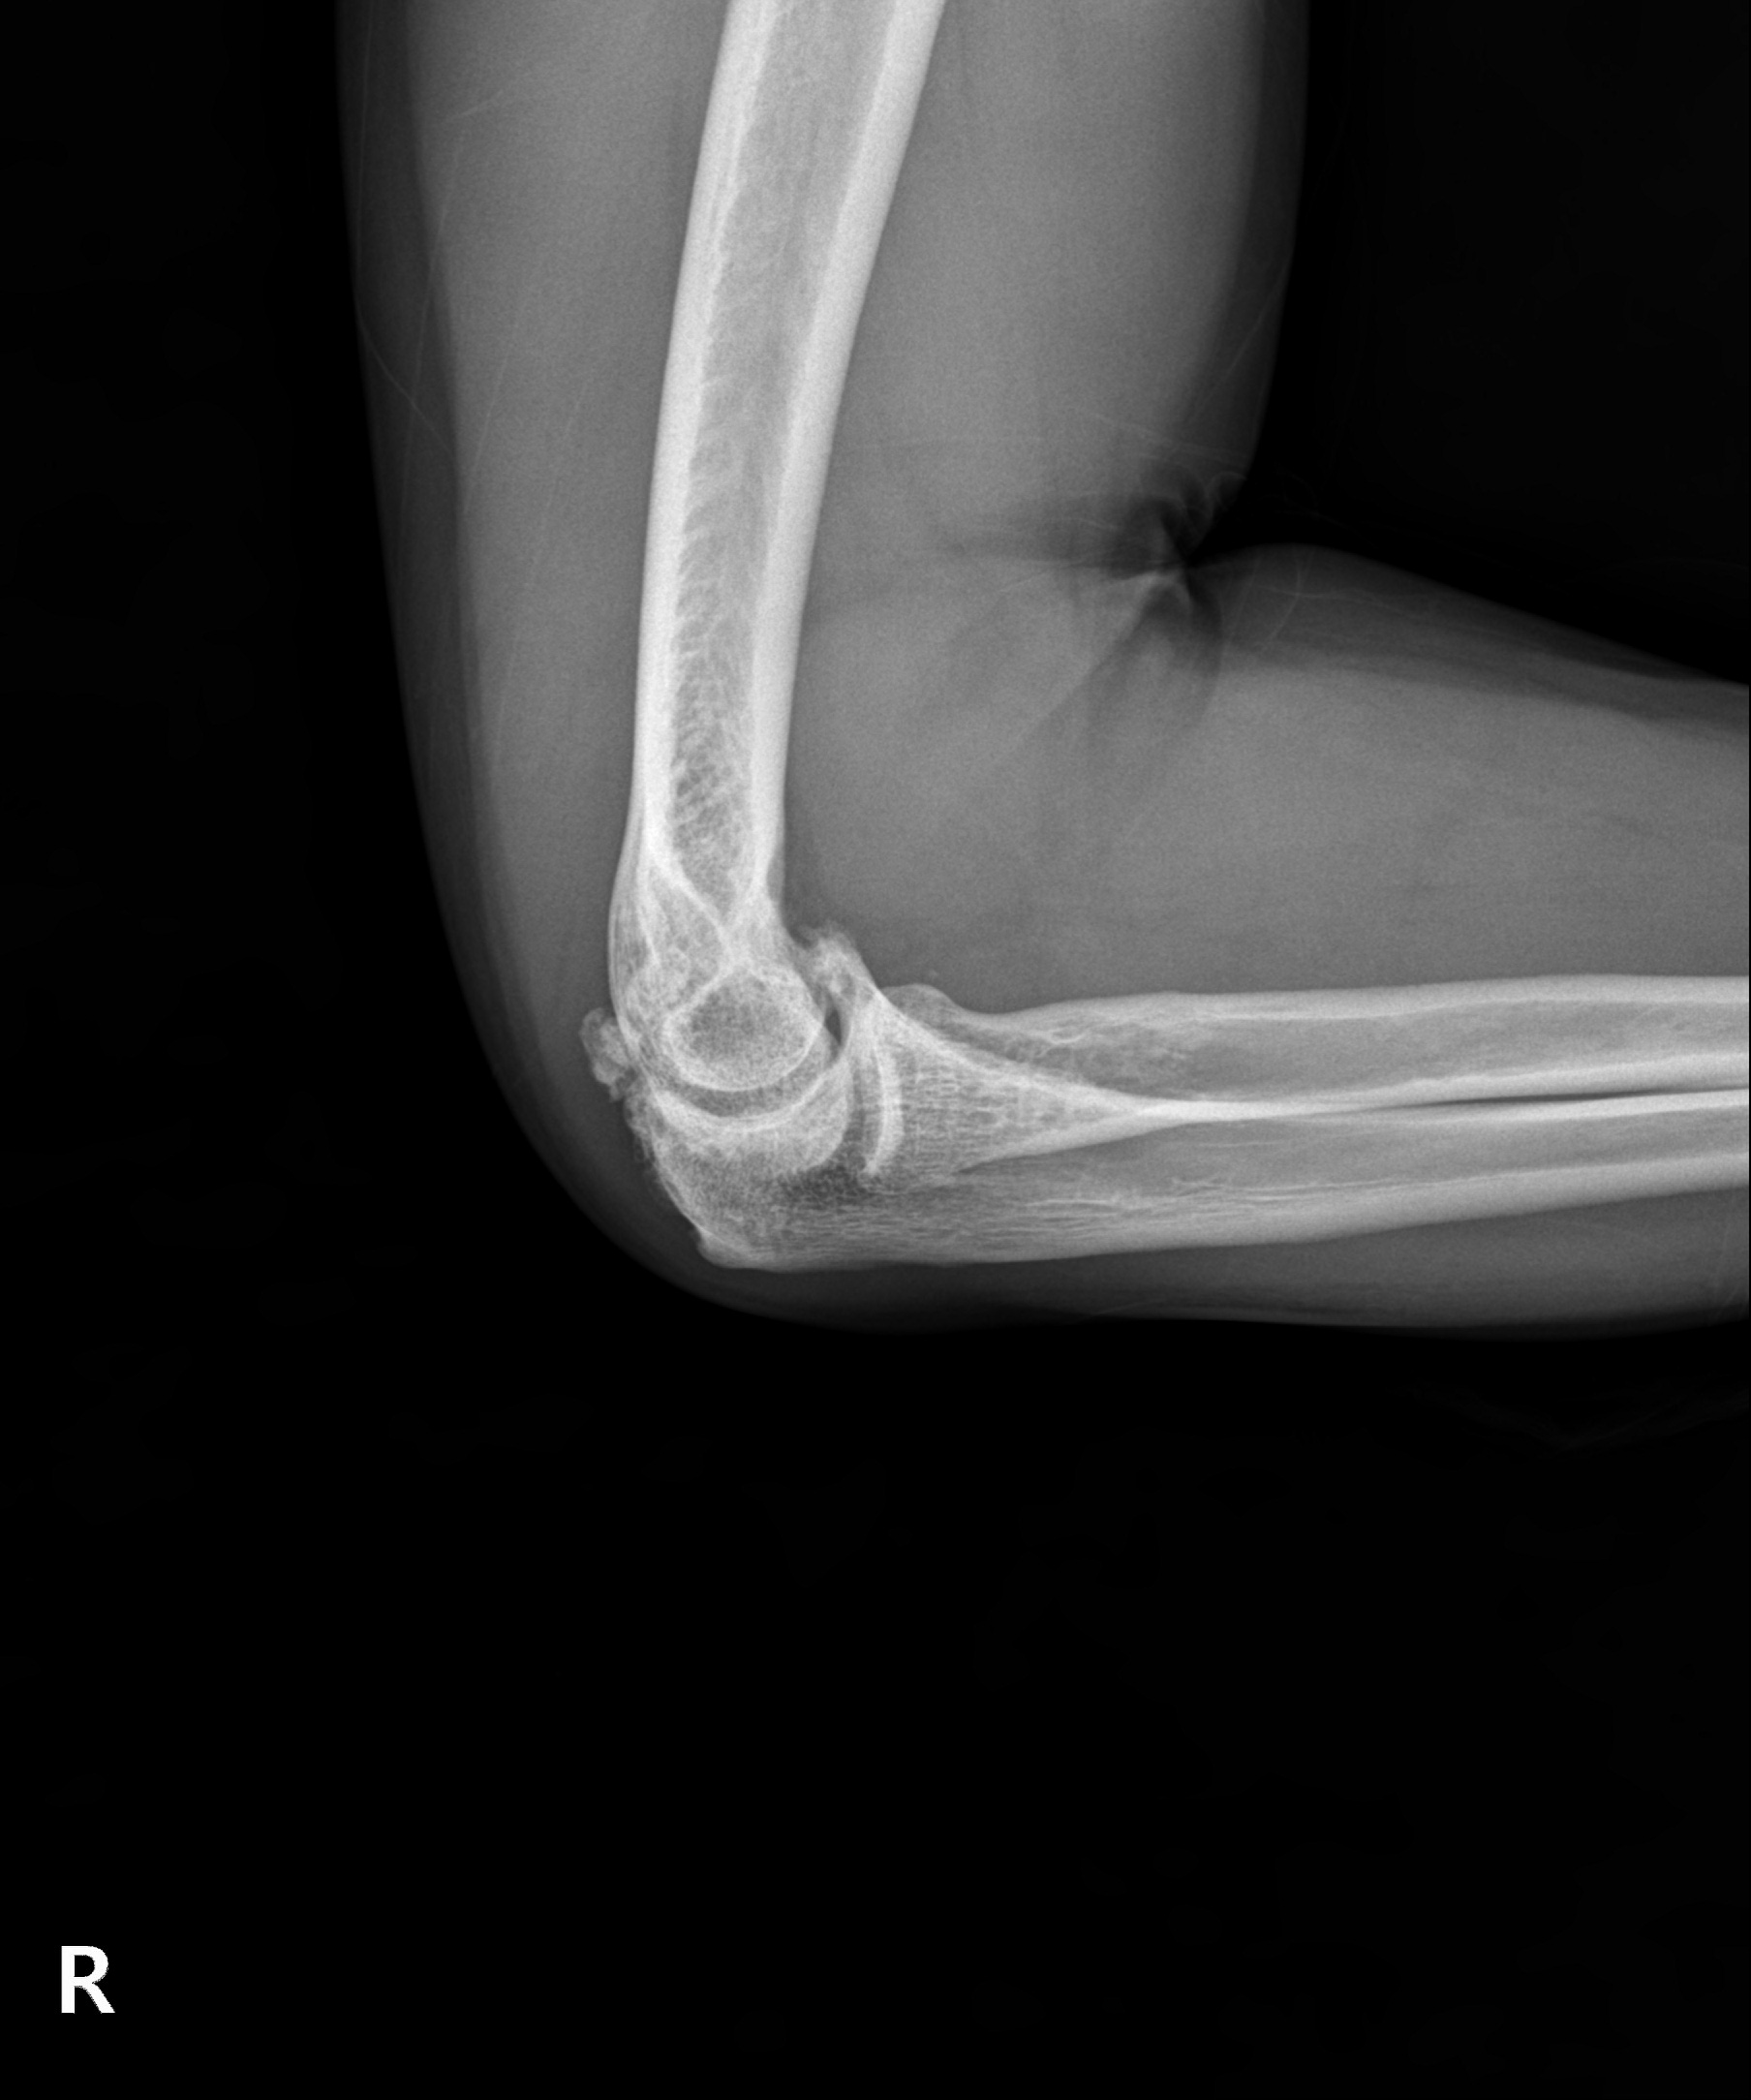

다른 부위 관절염처럼 팔꿈치 관절을 오랜 시간 과사용하여 관절이 손상되고 염증이 발생하는 질환입니다. 팔꿈치관절염은 시간이 지나며 점차 연골이 닳고 뼈가 자라나는 골극이 발생해 관절 가동 범위가 줄어들며 변형과 통증을 악화시킬 수 있습니다.

이미 관절 가동 범위에 제한이 온 팔꿈치 관절염은 뼈가 자라고

유리체 등이 관절면을 덮은 경우가 대부분으로 수술적 치료가 필요

관절내시경을 통해 자라난 뼈 조각과 관절 내 유리체를 제거하며

심한 경우 절개 수술이 함께 필요할 수 있습니다.